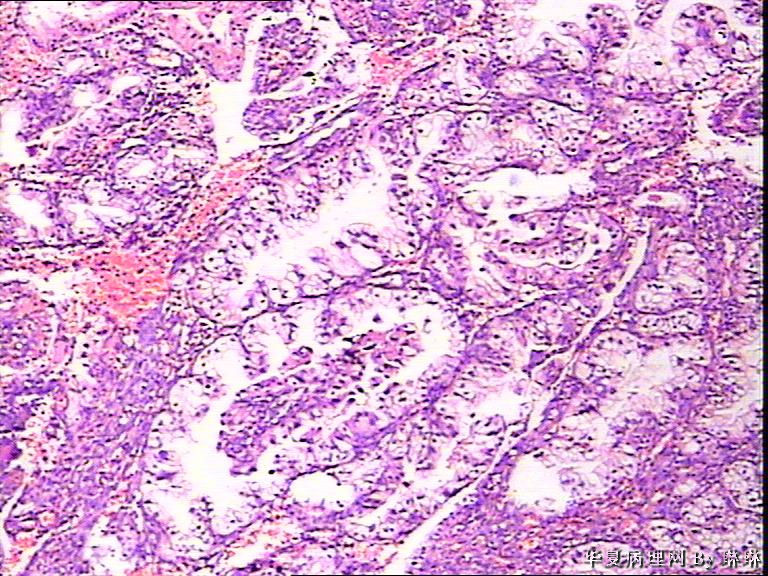

患者女性,38岁,月经量多4个月,曾服用止血药物,无其他病史。

• 子宫内膜,请教图1

图1

开始临床没有提供怀孕的病史,后来我们有咨询临床科室,大夫还是说没有用药、月经正常,刚过了经期,月经量多,这次月经持续时间长入院。所以我们开始排除了高度分泌的A-S反应,看到腺体增生呈乳头状,还有异型性,而且镜下部分子宫内膜还有增生期改变的,不完全是高度分泌的。再三考虑后还是要求临床查了血HCG,结果显示HCG370多。最后我们发了单纯性增生伴高度分泌。

腺体呈高度分泌反应,我们必须结合病史,考虑是否药源性反应,或持续黄体期子宫内膜.

晚泌期宫内膜,并见A-S现象

复杂性增生伴分泌反应